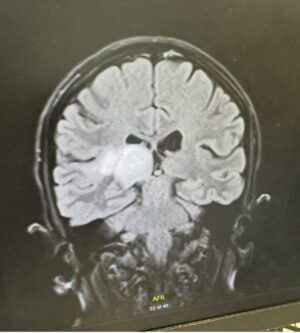

A thalamus glioma is a rare type of brain tumour located deep within the brain. Because of its position in the thalamus—an area that controls important functions—surgery is often difficult or too risky.

However, the tumour was still believed to be a glioma, and it was located in the thalamus — a deep part of the brain that acts as a central relay for signals.

Because of this location, surgery was not possible.

A thalamus glioma is a rare brain tumour located deep in the brain, often making surgery difficult or unsafe.

In many cases, surgery is not possible due to the tumour’s location in the brain.